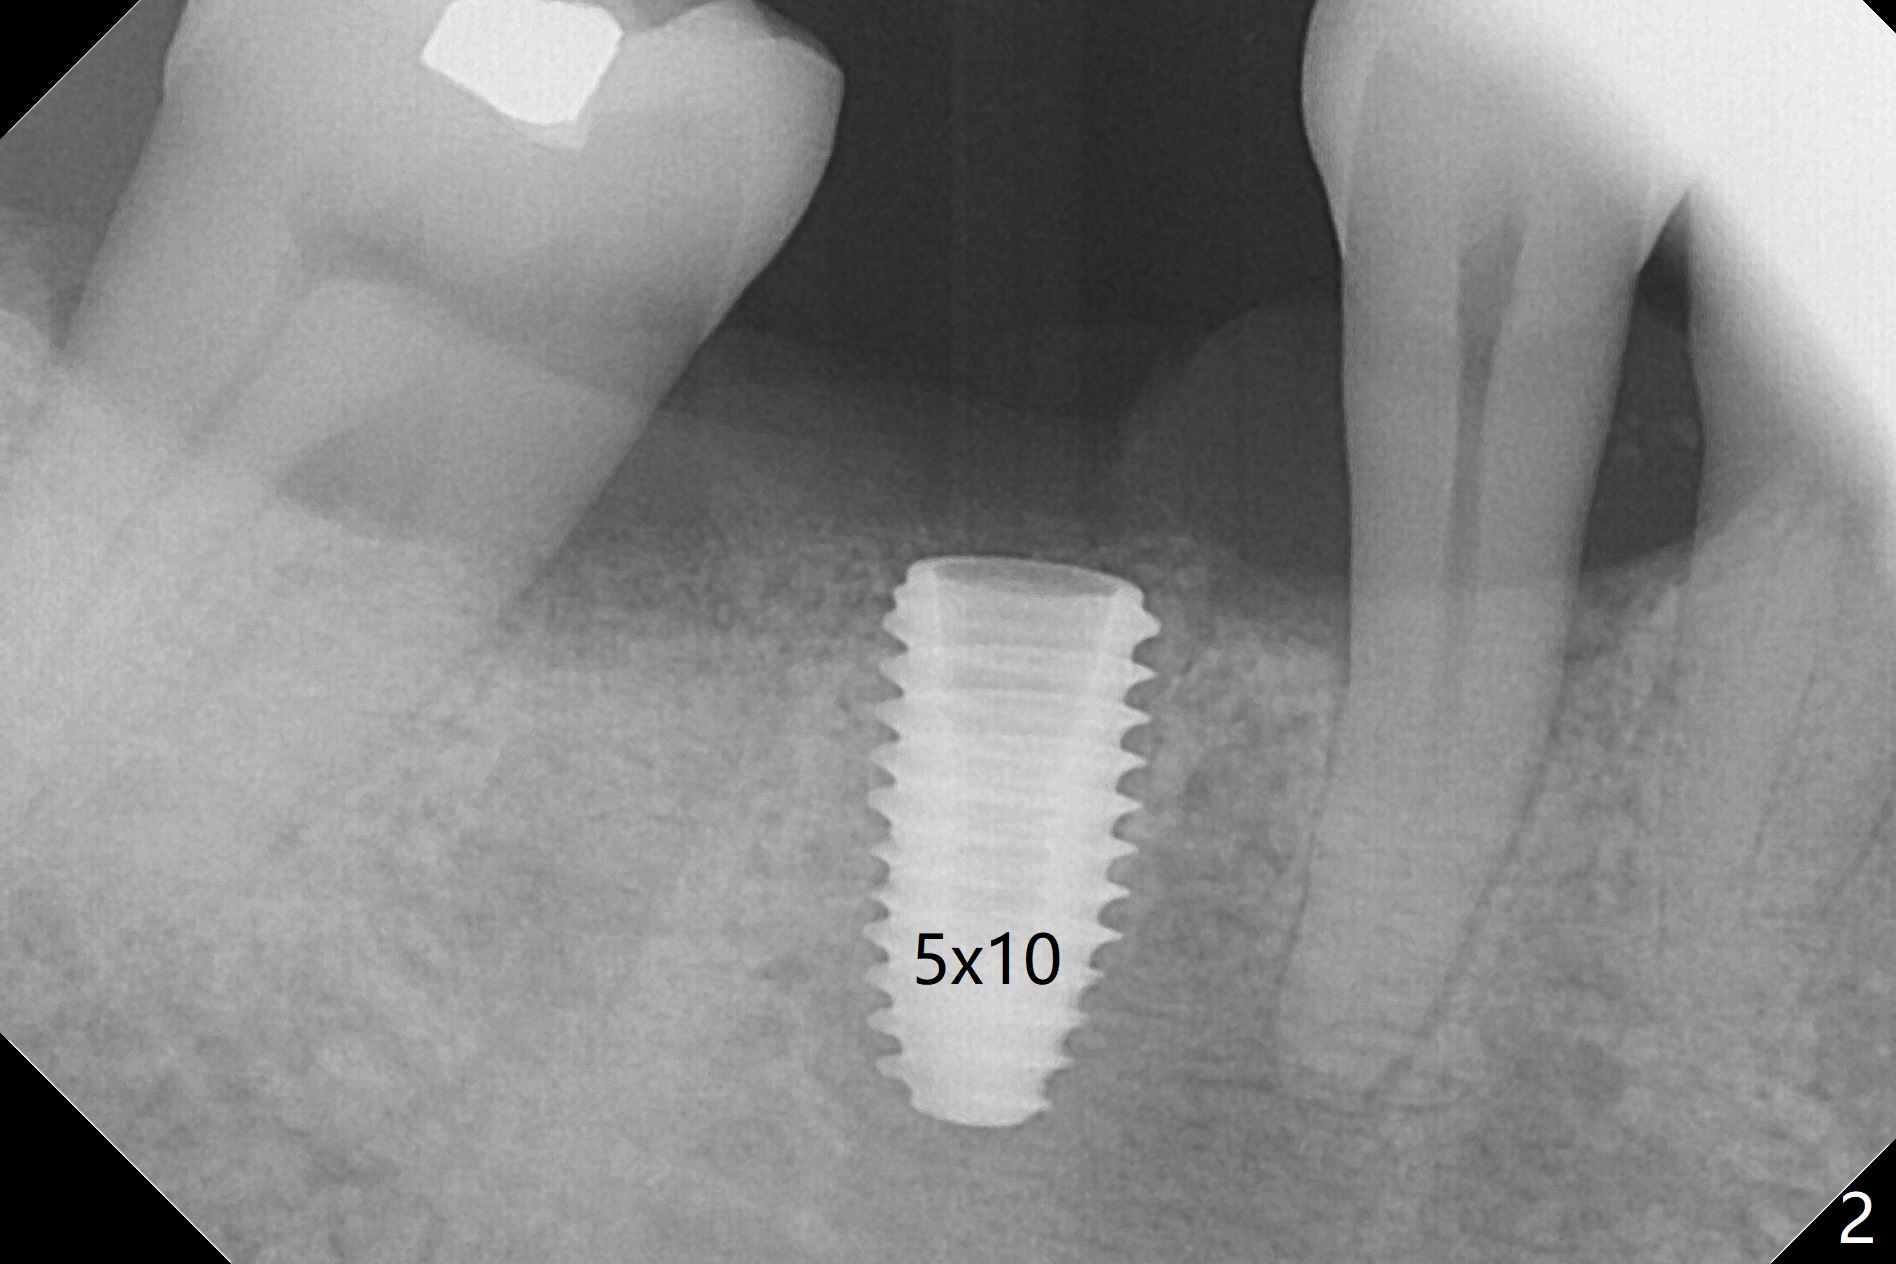

There are two questions before guided surgery at #30.  First, is implant placement 3 months post socket preservation too early?  Will the periapical radiolucency between #29 and #30 affect osteointegration?  Reanalysis of CT >2 months post socket preservation reveals that the lamina dura of the tooth #29 is apparently intact (Fig.1).  Immediately preop clinical exam shows no active infection.  The patient is reluctant to accept RCT at #29.  A 5x10 mm implant is placed slightly subcrestal buccally (which is the lowest, Fig.2).  Immediately postop CT (5x5cm field of view) demonstrates that the implant is covered by graft bone (Fig.3 *) buccally (B).  In fact the autogenous bone harvested from osteotomy is inserted between the 6x4 mm healing abutment and the buccal gingiva.